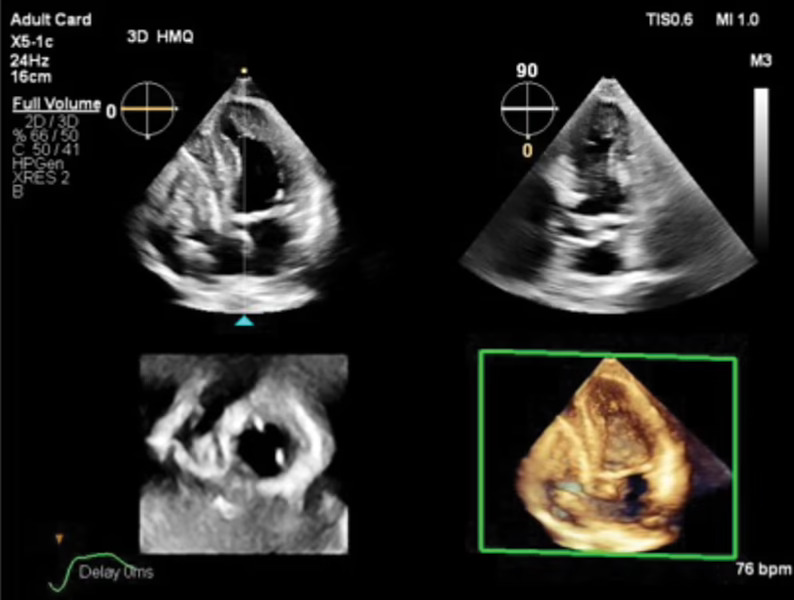

Transcend Plus ofrece avances 2D y 3D y mejora la eficiencia mediante 26 aplicaciones de IA integradas. Su nueva función 2D Auto EF Advanced incrementa las capacidades de análisis automático de la función ventricular izquierda.